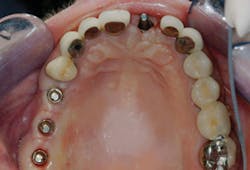

Observe the implant abutments in Fig. 4. The three in the posterior area have had separate abutments placed on them, each with a screw holding the abutment in place on the implant. That technique was not necessary. The implants are approximately in the center of the crowns to be placed over them, and they are nearly perpendicular to what will become the occlusal plane. They could easily have had crowns screwed directly to the implants without a separate abutment. When observing the central incisor with an unaltered manufacturer-made abutment, it is apparent that the abutment is too far facial and will require significant reduction to allow proper thickness of the porcelain-fused-to-metal crown to be placed. Because of this usual bone anatomy angulation in the anterior maxilla, the central incisor is a candidate for a custom abutment, and a four-piece restoration with the crown cemented to the separate abutment.